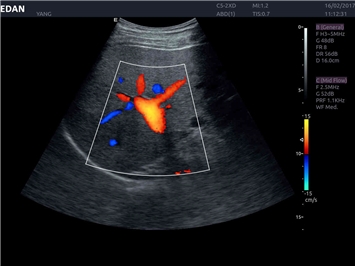

• Тканевая допплеровская визуализация (TDI)

• Кардиологических исследований

Трехмерная реконструкция ЦДК:

Да